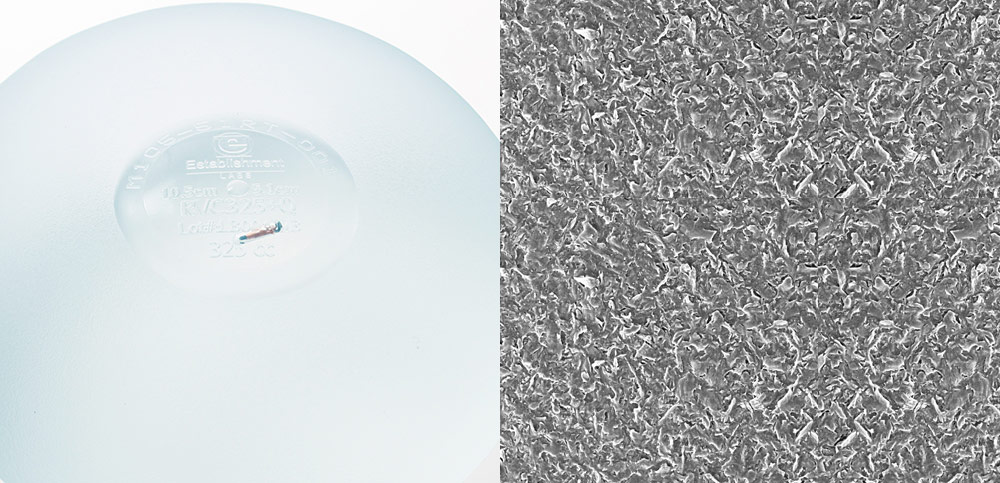

如果真的很在意莢膜攣縮的風險,絨毛面果凍(包含水滴型跟圓形絨毛面)可以有效控制這個問題,這是如何達成的呢?

我們如果仔細看絨毛面,不論是哪家公司製造的,從顯微鏡下都可以明顯看到很多不規則的毛狀組織。可以讓我們胸部的組織長入,因為不規則的形狀會將接觸面大幅上升,所以不容易產生收縮的情形。